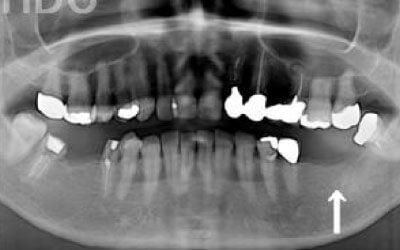

骨が薄い場合、そのままインプラントを行うのはお勧めできません。

ただし、事前に骨を増やす治療を行ったり、インプラントと同時に骨を増やす治療を行えば、インプラントは可能です。

特に、抜けたのが前歯ですとなおさら気になりますよね。 今回のご質問ですが、抜けた部分の骨が薄いなどの理由で「インプラントはできない」と言われた可能性があります。

前歯はもともと骨が薄く、歯が抜けると時間の経過とともにさらに骨が痩せてきてしまうので、インプラント治療の難易度が高い場所です。 ただ結論からお話すると、インプラント治療は可能です。

なぜなら、もし仮に骨が薄くても、骨の治療によって厚みが増せば、安全にインプラント治療が行えるからです。

なお、前歯のインプラント治療をご希望の方には、注意していただきたい点が4つほどあります。 1)インプラント治療を行う前に、骨の治療が必要かもしれません。

2)骨の治療から始めると、その分、治療期間が長くなります。

3)骨の治療は、通常のインプラント治療よりも難易度が高いため、経験の豊富な先生やインプラント認定医のいる歯科医院で治療を受けることをお勧めします。

4)骨の状況をしっかり把握するためにも、CT撮影が必須となります。 また、インプラント治療においては、周囲の歯の状況や咬み合わせの問題などもしっかりと考えて治療するのがとても大切です。